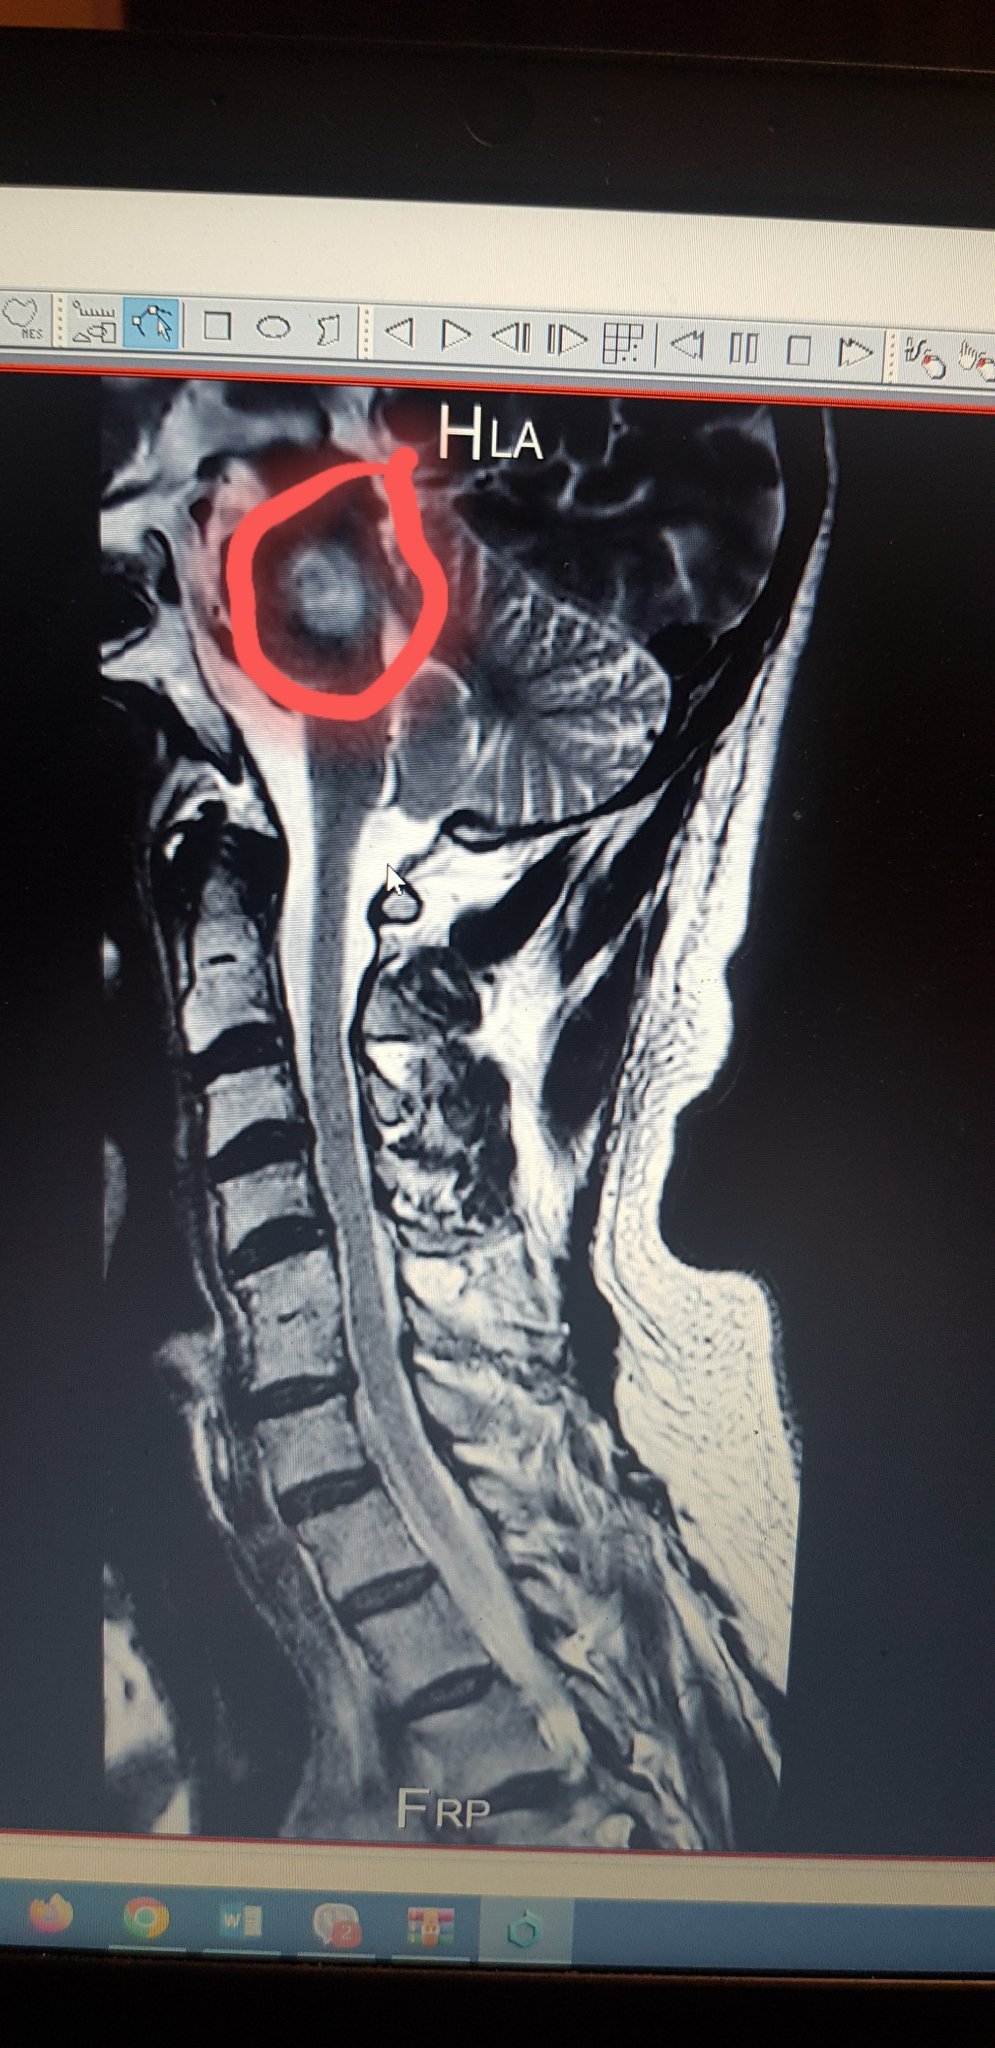

Пускам и разчета на ЯМР

всъщност нямате цял резонанс на глава. Имате може би  ствола, хванат при резонанс на шията. От двата реда по-долу пише, че болният е приет в неврохирургия и резонансът е правен там, основно - шия. Т. е е бил е приет заради шията? и тези лезии са случайна находка?

Да, точно така, открити са случайно по повод преглед на определени шийни прешлени, за да се търси от къде идва изтръпването в ръката и крака. Невролог ни насочи и така стана съвсем случайно. Но пък на самия диск се вижда и главата.....Главно искаха да видят прешлените.Ще пусна снимка на едната лезия, която ми показа невеохирургът.